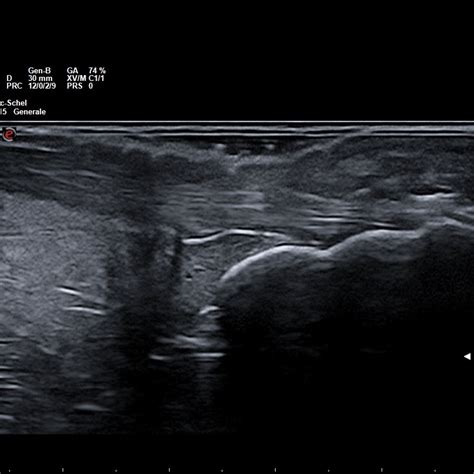

Ecografia Muscoloscheletrica (Ecografia Articolare): L'ecografia articolare si rivela uno strumento prezioso per la diagnosi precoce dell'artrite psoriasica. Permette di identificare segni di infiammazione a carico delle articolazioni e dei tendini anche prima che i sintomi siano evidenti o rilevabili alla radiografia convenzionale. Questo esame può evidenziare iperemia sinoviale, versamenti articolari e tenosinovite, confermando la presenza di un processo infiammatorio attivo.

Ecografia muscolo-scheletrica nella diagnosi precoce in reumatologia